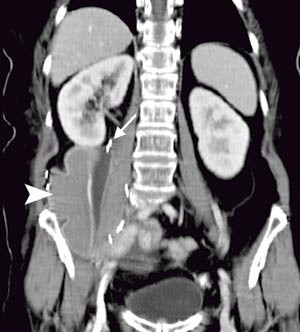

Pasienten. En tidligere frisk kvinne ble som 68-åring operert for cancer coeci med perforasjon. Det forelå en perikolisk abscess, og det ble gjort høyresidig hemikolektomi med reseksjon av fremre bukvegg. Inngrepet ble ansett som radikalt. I operasjonspreparatet fant man spredning til regionale lymfeknuter (Dukes C), og hun fikk derfor adjuvant kjemoterapi med 5-fluorouracil/leukovorin i seks måneder. Ett år senere utviklet hun sterke smerter i høyre flanke med utstråling til høyre lår, og ved CT ble det påvist en 12 cm stor tumor som infiltrerte m. iliopsoas dexter, oppfattet som et lokoregionalt residiv (fig 1). Det var ingen fjernmetastaser. Residivet ble resecert i muskulatur ved laparotomi, men tumorvev måtte etterlates omkring iliacakarene. Svulsten omsluttet n. femoralis, som måtte deles. Tumorsengen ble markert med metallklyper, og en brystprotese i silikon ble lagt på reseksjonsflaten for å skyve tynntarmen vekk fra det påtenkte strålefeltet (fig 2). Postoperativ CT viste likevel en interponert tarmslynge mellom protesen og fremre bukvegg (fig 3). Seks uker etter inngrepet ble det påbegynt radiokjemoterapi med 2 Gy x 25 som to motgående skråfelt og strålesensibiliserende 5-fluorouracil/leukovorin (fig 3). Under bestrålingen utviklet kvinnen høyresidig bekkenvenetrombose, og hun fikk antikoagulasjonsbehandling. Radioterapien var ledsaget av periodevise buksmerter, men uten diaré eller andre tegn til akutt stråleenteritt. Åtte uker etter endt bestråling ble hun igjen laparotomert. Den nevnte tarmslyngen frembød da ganske uttalte stråleskader. Protesen lot seg fjerne, i hovedsak ved stump disseksjon (fig 4). Pasienten ble likevel påført en ureterskade, som kunne repareres umiddelbart. Det var ingen gjenværende tumor, verken makro- eller mikroskopisk.